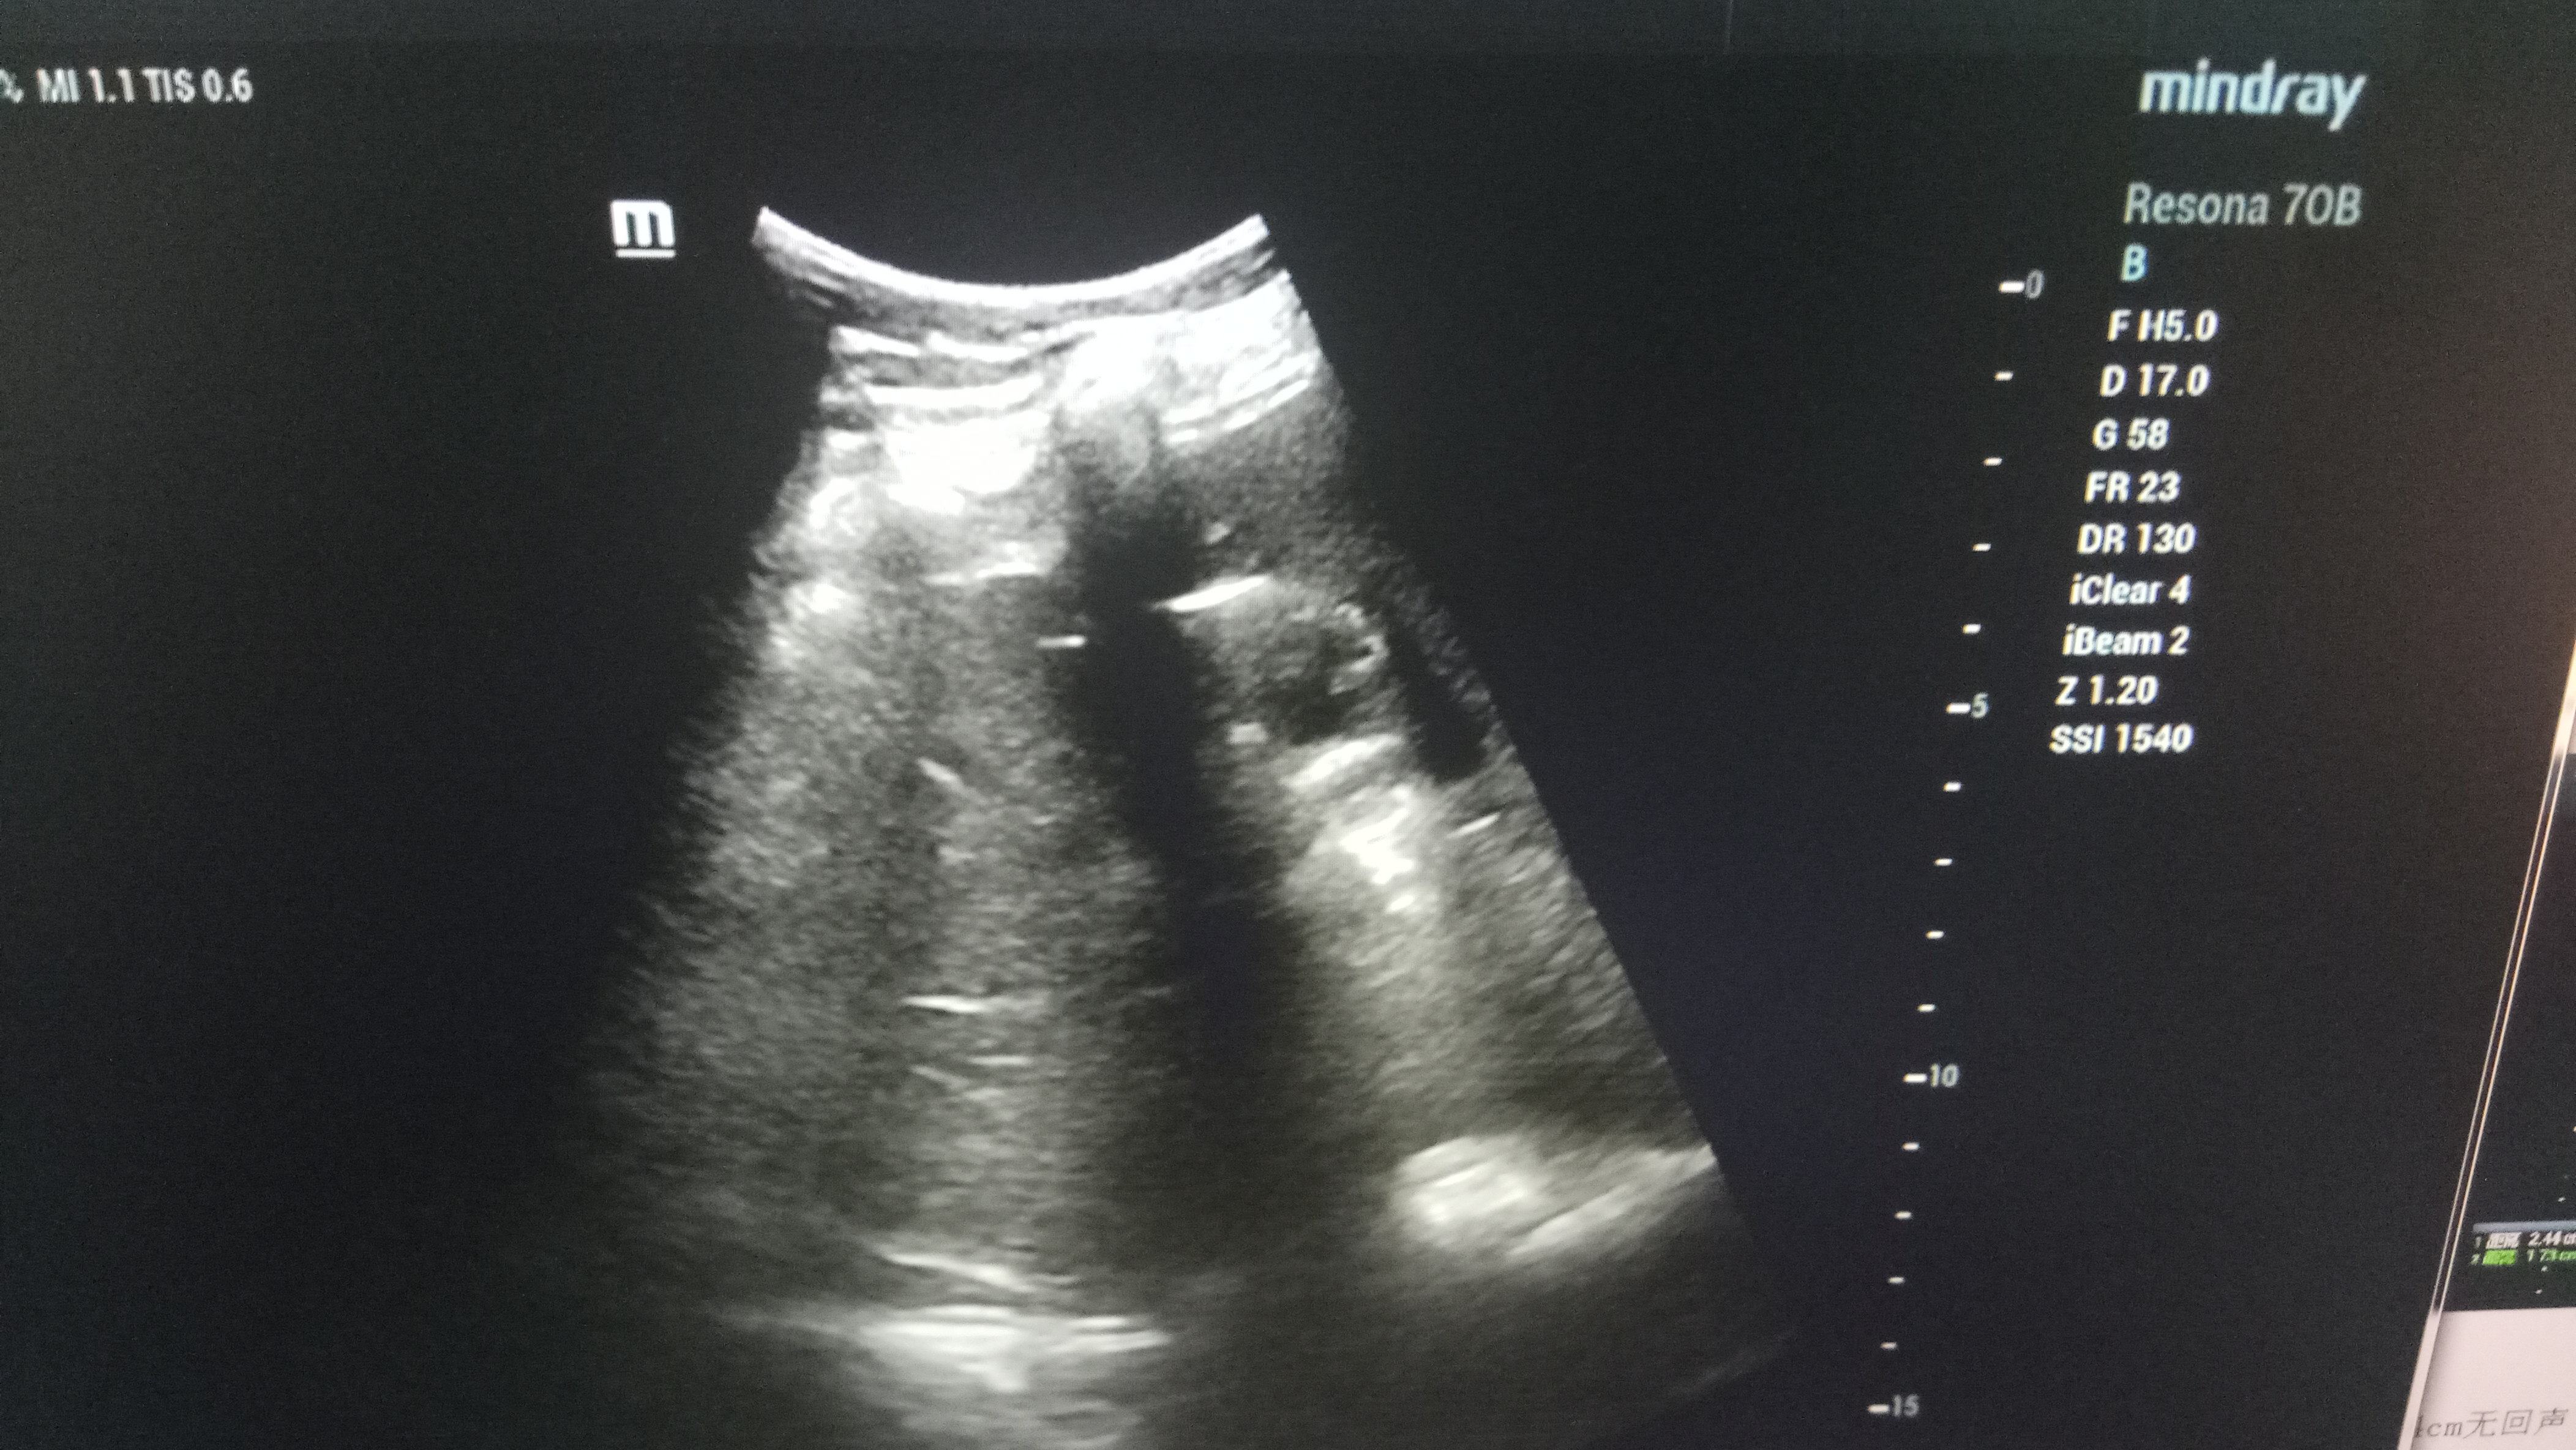

近日,探花av 超声科在高陵区医院成功开展了一例超声引导下肝囊肿抽吸硬化治疗术。患者前段时间查出肝囊肿,因开腹手术风险性大且痛苦,遂联系了高陵区医院超声科,在探花av 超声科主任展小军与对口支援医生杨艳秋的紧密配合下,短短30分钟,通过一根穿刺针,直径近7cm的肝囊肿就被完全抽吸硬化完毕,患者生命体征平稳,休息几小时后已活动自如。

超声介入微创诊疗技术是在实时超声的监视和引导下,完成各种穿刺、活检以及抽吸、插管、注药治疗等操作,达到与外科手术相当的效果,具有创伤小、恢复快、无辐射、介入治疗定位精确等优点。可治疗全身各部位囊肿,尤其是巧克力囊肿效果更佳,还有全身各部位肿瘤的活检和治疗,超声引导下微创治疗是未来医学发展方向。